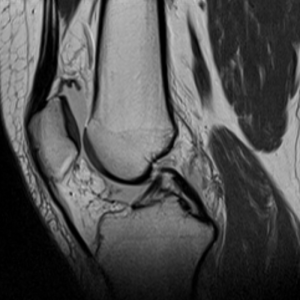

Det är bra att ha en rutin för hur man läser röntgenbilder generellt, även för MR-bilder. Ett exempel för knä kan vara så här:

Identifiera vilket som är lateralt (där man ser fibula). Börja laterala och gå mot medialt

Bläddra från ventralt till dorsalt, tillbaka till ventralt, upprepa vid behov.

Superiort till inferiort